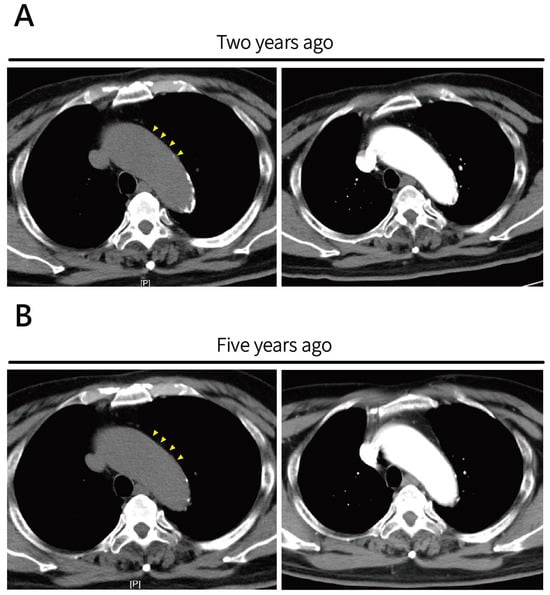

2. Case Presentation